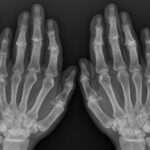

[doctormodu]1 hand OA

04 손가락 관절염 hand OA